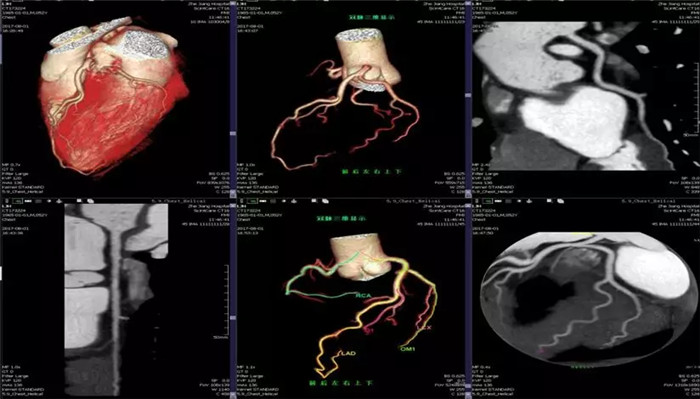

全域精圖

·心臟掃描應(yīng)用

·全面臨床功能